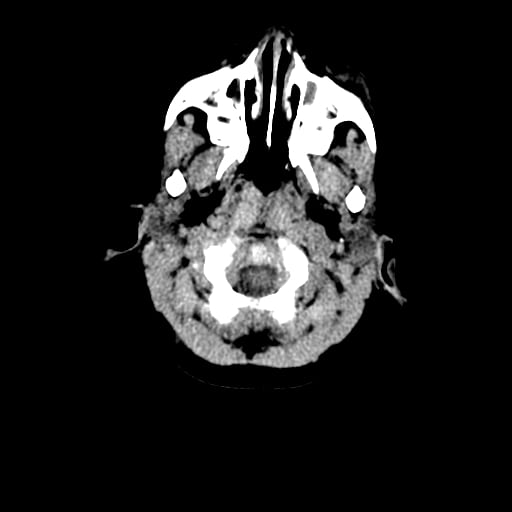

Age: 1

Sex: Male

Indication: Fall